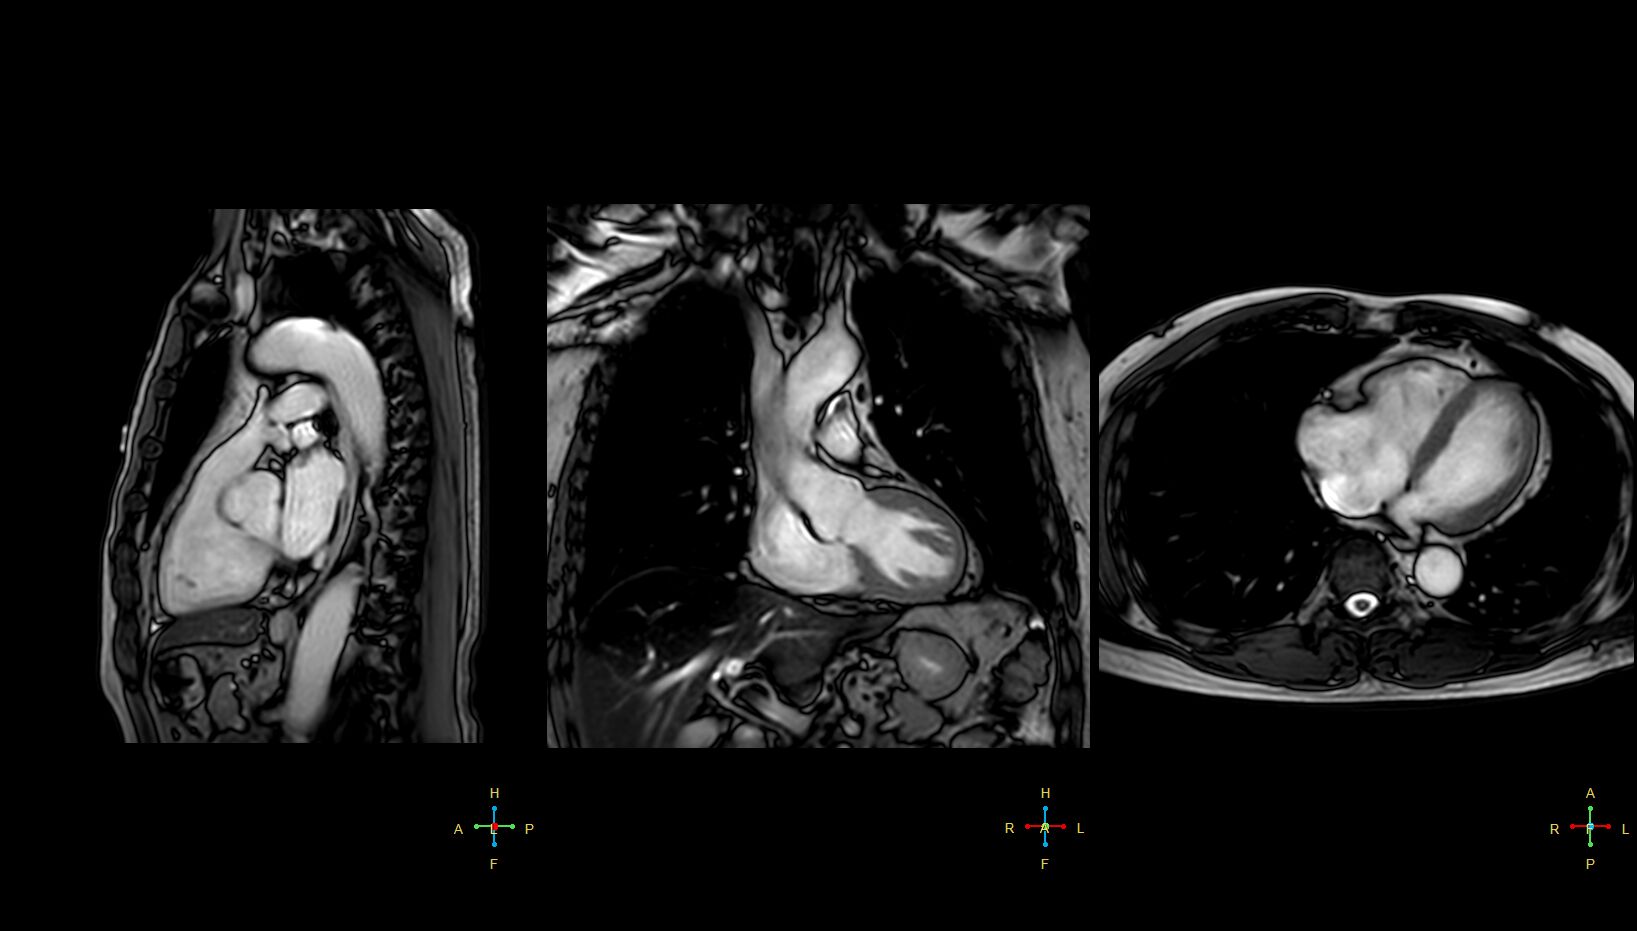

(Structure)用B-TFE 影大FOV Ax , Cor Sag

(Structure , Function)Cine , 動態影片,可以切出你想看結構,主要有4CH ,2CH ,SA, 2Ch , LVOT , RVOT ,Aortic valve ,R-2ch